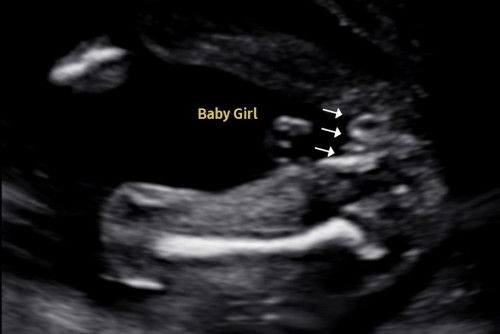

usg 19w + ftm 🥹

guys, ni baby girl ke baby boy eh? sono cakap baby girl sebab ada 3 line tapi saya nampak macam telur aje kat tengah tu 😰 nak beli baju pun teragak agak lagi sekarang takut nanti 5d scan gender lain. confirm eh girl? 🥹 ftm here! #bantujawab #askmommies #askmommies